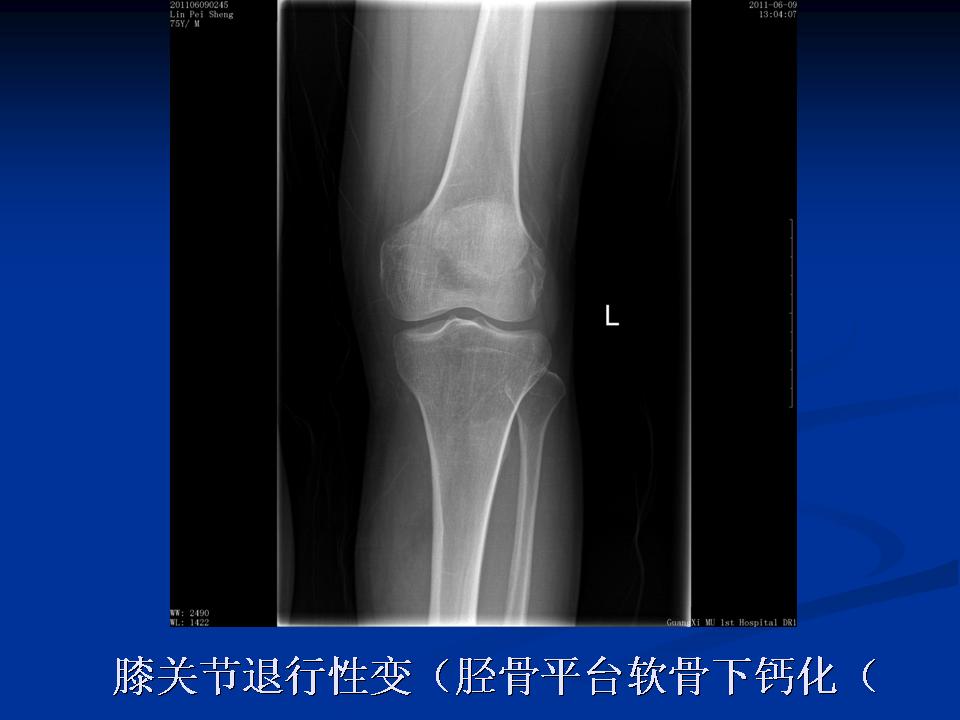

影像学检查 X线 四个方向X线影像 l 早期可无改变 l关节间隙变窄、不均匀、消失(成人<3mm; 老年人<2mm)。 l骨赘形成 l关节内游离体、骨质疏松 l软骨下骨板硬化、囊性变

膝关节退行性变(胫骨平台软骨下钙化)